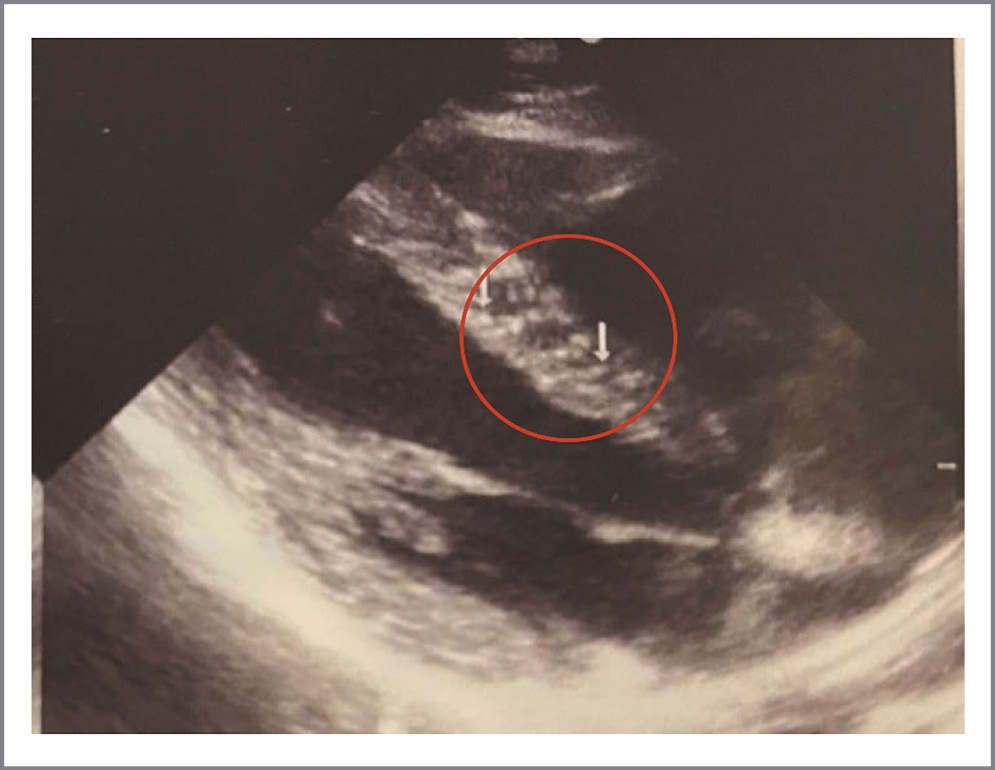

Изменения в миокарде представлены в виде округлых гиперэхогенных, единичных или немногочисленных диффузно расположенных включений от 1,5 до 3,2 мм в диаметре, локализующихся в основном в межжелудочковой перегородке или в толще задней стенки ЛЖ (рис. 4). Эти включения визуально отличались от обычно выявляемых участков мелкоочагового фиброза, например после перенесенного миокардита или при ишемической болезни сердца и кардиосклерозе, когда очаги носят преимущественно линейный характер (рис. 5). Относительно диастолической дисфункции достаточно сложно сделать однозначный вывод, так как к данному состоянию могут приводить различные факторы. Однако наличие включений в миокарде, которые гипотетически могут быть последствиями специфического миокардита или изменениями на фоне перенесенного ТМА-подобного состояния при COVID-19, и гидроперикарда соотносятся с результатами немецкой когорты пациентов [37]. Важно отметить, что обнаружение описанных изменений требует от специалиста ультразвуковой диагностики высокой квалификации и достаточного уровня насмотренности. В течение периода набора данных в поле зрения также попал пациент 21 года, не болевший COVID-19, но у которого по данным ЭхоКГ в миокарде обнаружена группа мелкоочаговых округлых гиперэхогенных включений до 2,5 мм с сохранной диастолической и систолической функцией (рис. 6).

Рис. 5. ЭхоКГ, парастернальная позиция, длинная ось ЛЖ, примеры линейных участков фиброза в межжелудочковой перегородке.

Fig. 5. EchoCG, parasternal position, left ventricle long axis, examples of linear areas of fibrosis in the interventricular septum.